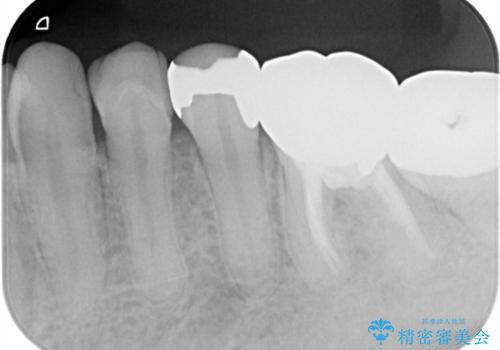

メタルインレーを除去したところ、二次カリエスうを確認したため除去・CR裏層の後、形成・印象しています。

セラミックインレーの接着操作時にはラバーダム防湿を行っています。